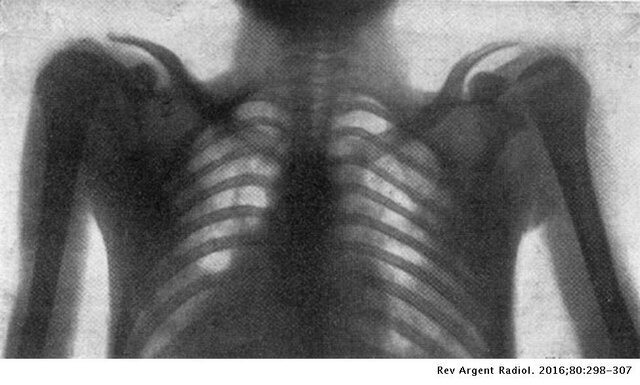

• 1era Rx de Torax in situ

1era Rx de Torax in situ

Fue hecha por el escocés John MacIntyre, con un tiempo de exposición de 60 minutos y radiografías bastante

borrosas.